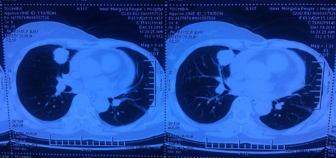

2016年11月,患者出现不适,复查PET-CT提示:1.右肺中叶内侧段结节,伴代谢增高,考虑恶性,转移可能性大。2.左肺上叶尖后段结节,伴代谢增高,考虑转移。未作治疗,继续随访。

诊断:左乳浸润性导管癌右肺转移(Ⅳ期)。